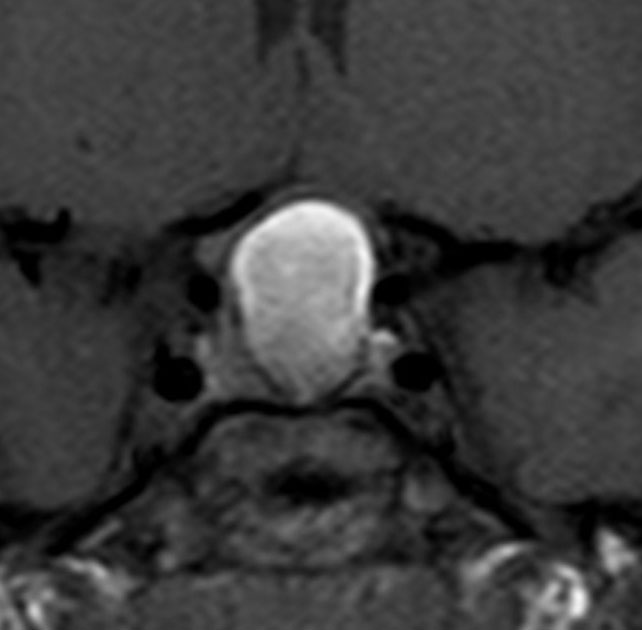

上のT2強調画像では,全体的に低信号で,高信号の部分が混在します。上右のCISS画像では,下垂体組織が右に変移していることが推定されます。

左がT1強調画像で高信号,右がT1ガドリニウム増強像ですが腫瘍は増強されません。正常か錐体が腫瘍の右側にくっついていて,ガドリニウム増強されています。典型的なトルコ鞍部黄色肉芽腫です。画像診断で,下垂体腺腫の腫瘍内出血とよく間違われるのですが,高信号になるのはコレステリン結晶を豊富に含むからです。ガドリニウム増強される部分がほとんどないという所見が頭蓋咽頭腫とは異なるところでしょう。

左と中央の画像でinfundibular recessの管腔が見え,左の視交差から視索の変形が強いことが解ります。右の画像では下垂体組織がトルコ鞍の右側に偏在してあります。画像では正常化錐体と明瞭な境界があるように見えるのですが,実際の手術所見では正常下垂体との境界は不鮮明でした。腫瘍のう胞からは黒褐色の内容液 machinery oil とコレステリン結晶が流出しました。厚いのう胞壁は硬膜と下垂体に強く付着して剥離するのが困難で切断して摘出しました。ラトケのう胞とはのう胞壁の厚さが異なると言えます。